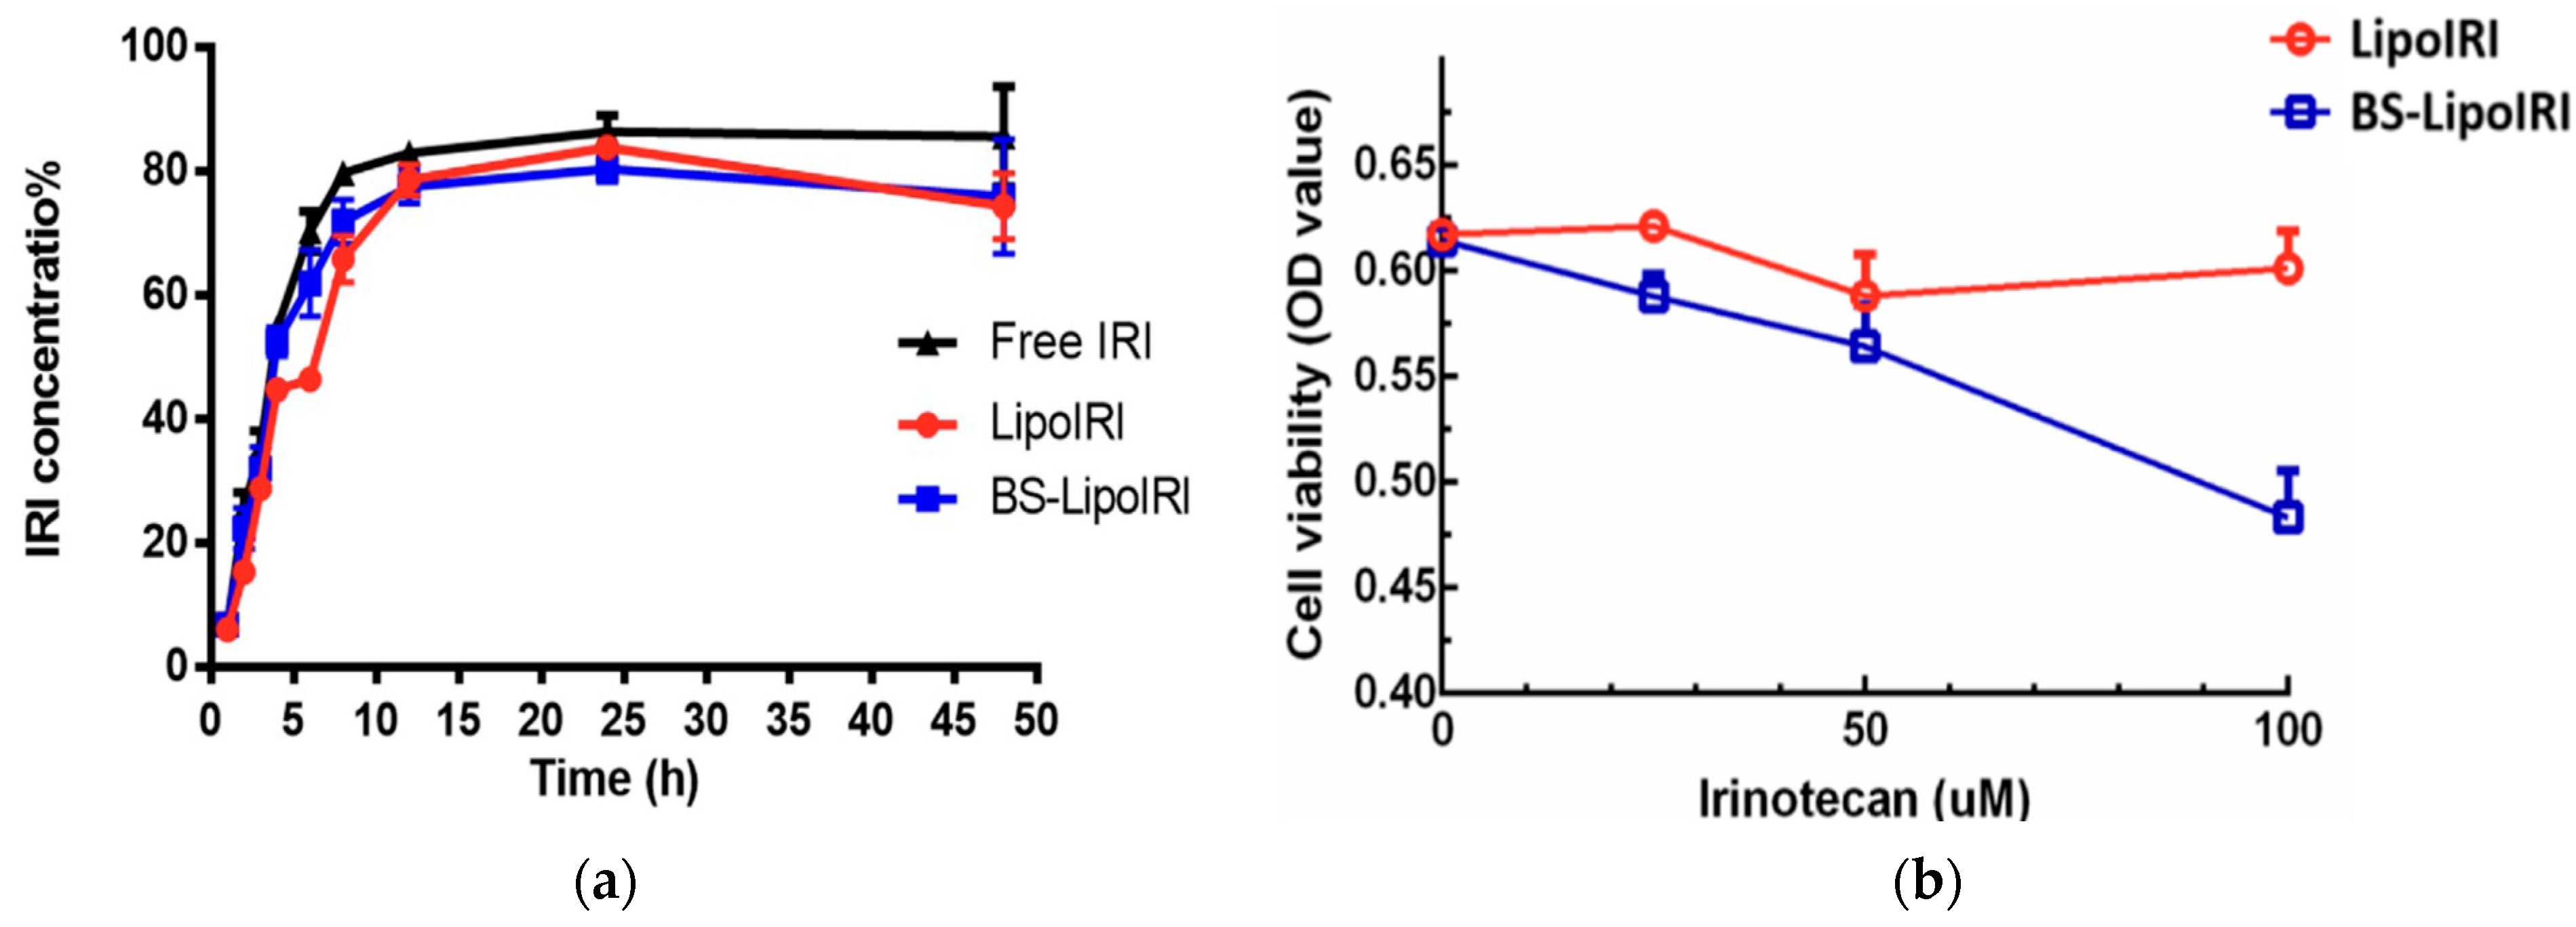

- Lin, H.-J.; Liang, T.-L.; Chang, Y.-Y.; Liu, D.-Z.; Fan, J.-Y.; Roffler, S.R.; Lin, S.-Y. Development of Irinotecan Liposome Armed with Dual-Target Anti-Epidermal Growth Factor Receptor and Anti-Fibroblast Activation Protein-Specific Antibody for Pancreatic Cancer Treatment. Pharmaceutics 2022, 14, 1202. [Google Scholar] [CrossRef] [PubMed]

| Liposomes (BS-LipoIRI) | Irinotecan | Particle size = 125 nm; drug encapsulation efficiency = 80.95% | Epidermal growth factor receptor (EGFR) and fibroblast activation protein bispecific antibody | Pancreatic tumor cells and tumor-associated fibroblasts | Eight-week-old SCID mice | Human Pancreatic Tumor | [118] |